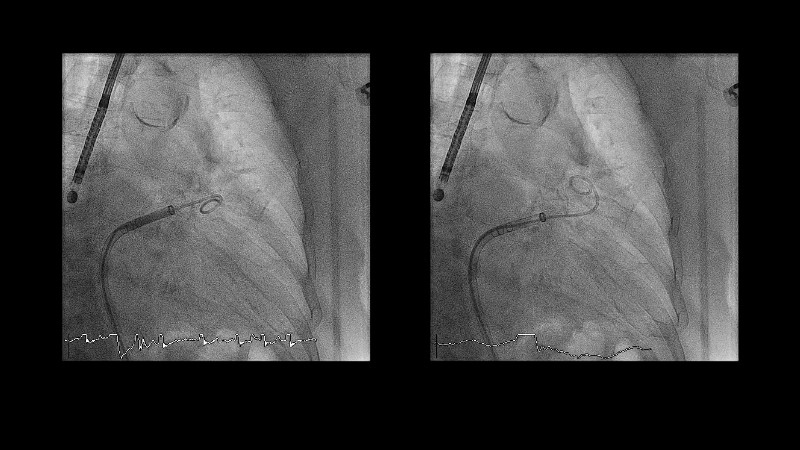

Explore the forefront of left atrial appendage (LAA) closure with this session focusing on the latest innovations and clinical opportunities. Topics include recent data on WATCHMAN FLX PRO and VersaCross Connect systems, workflow strategies to improve procedural efficiency, and discussions on upcoming clinical trials such as CHAF and LAAOS IV, emphasizing expanding stroke prevention options beyond bleeding risk reduction.

- To learn workflow strategies to improve efficiencies for LAA closure - VersaCross Connect + PRO + TruSteer